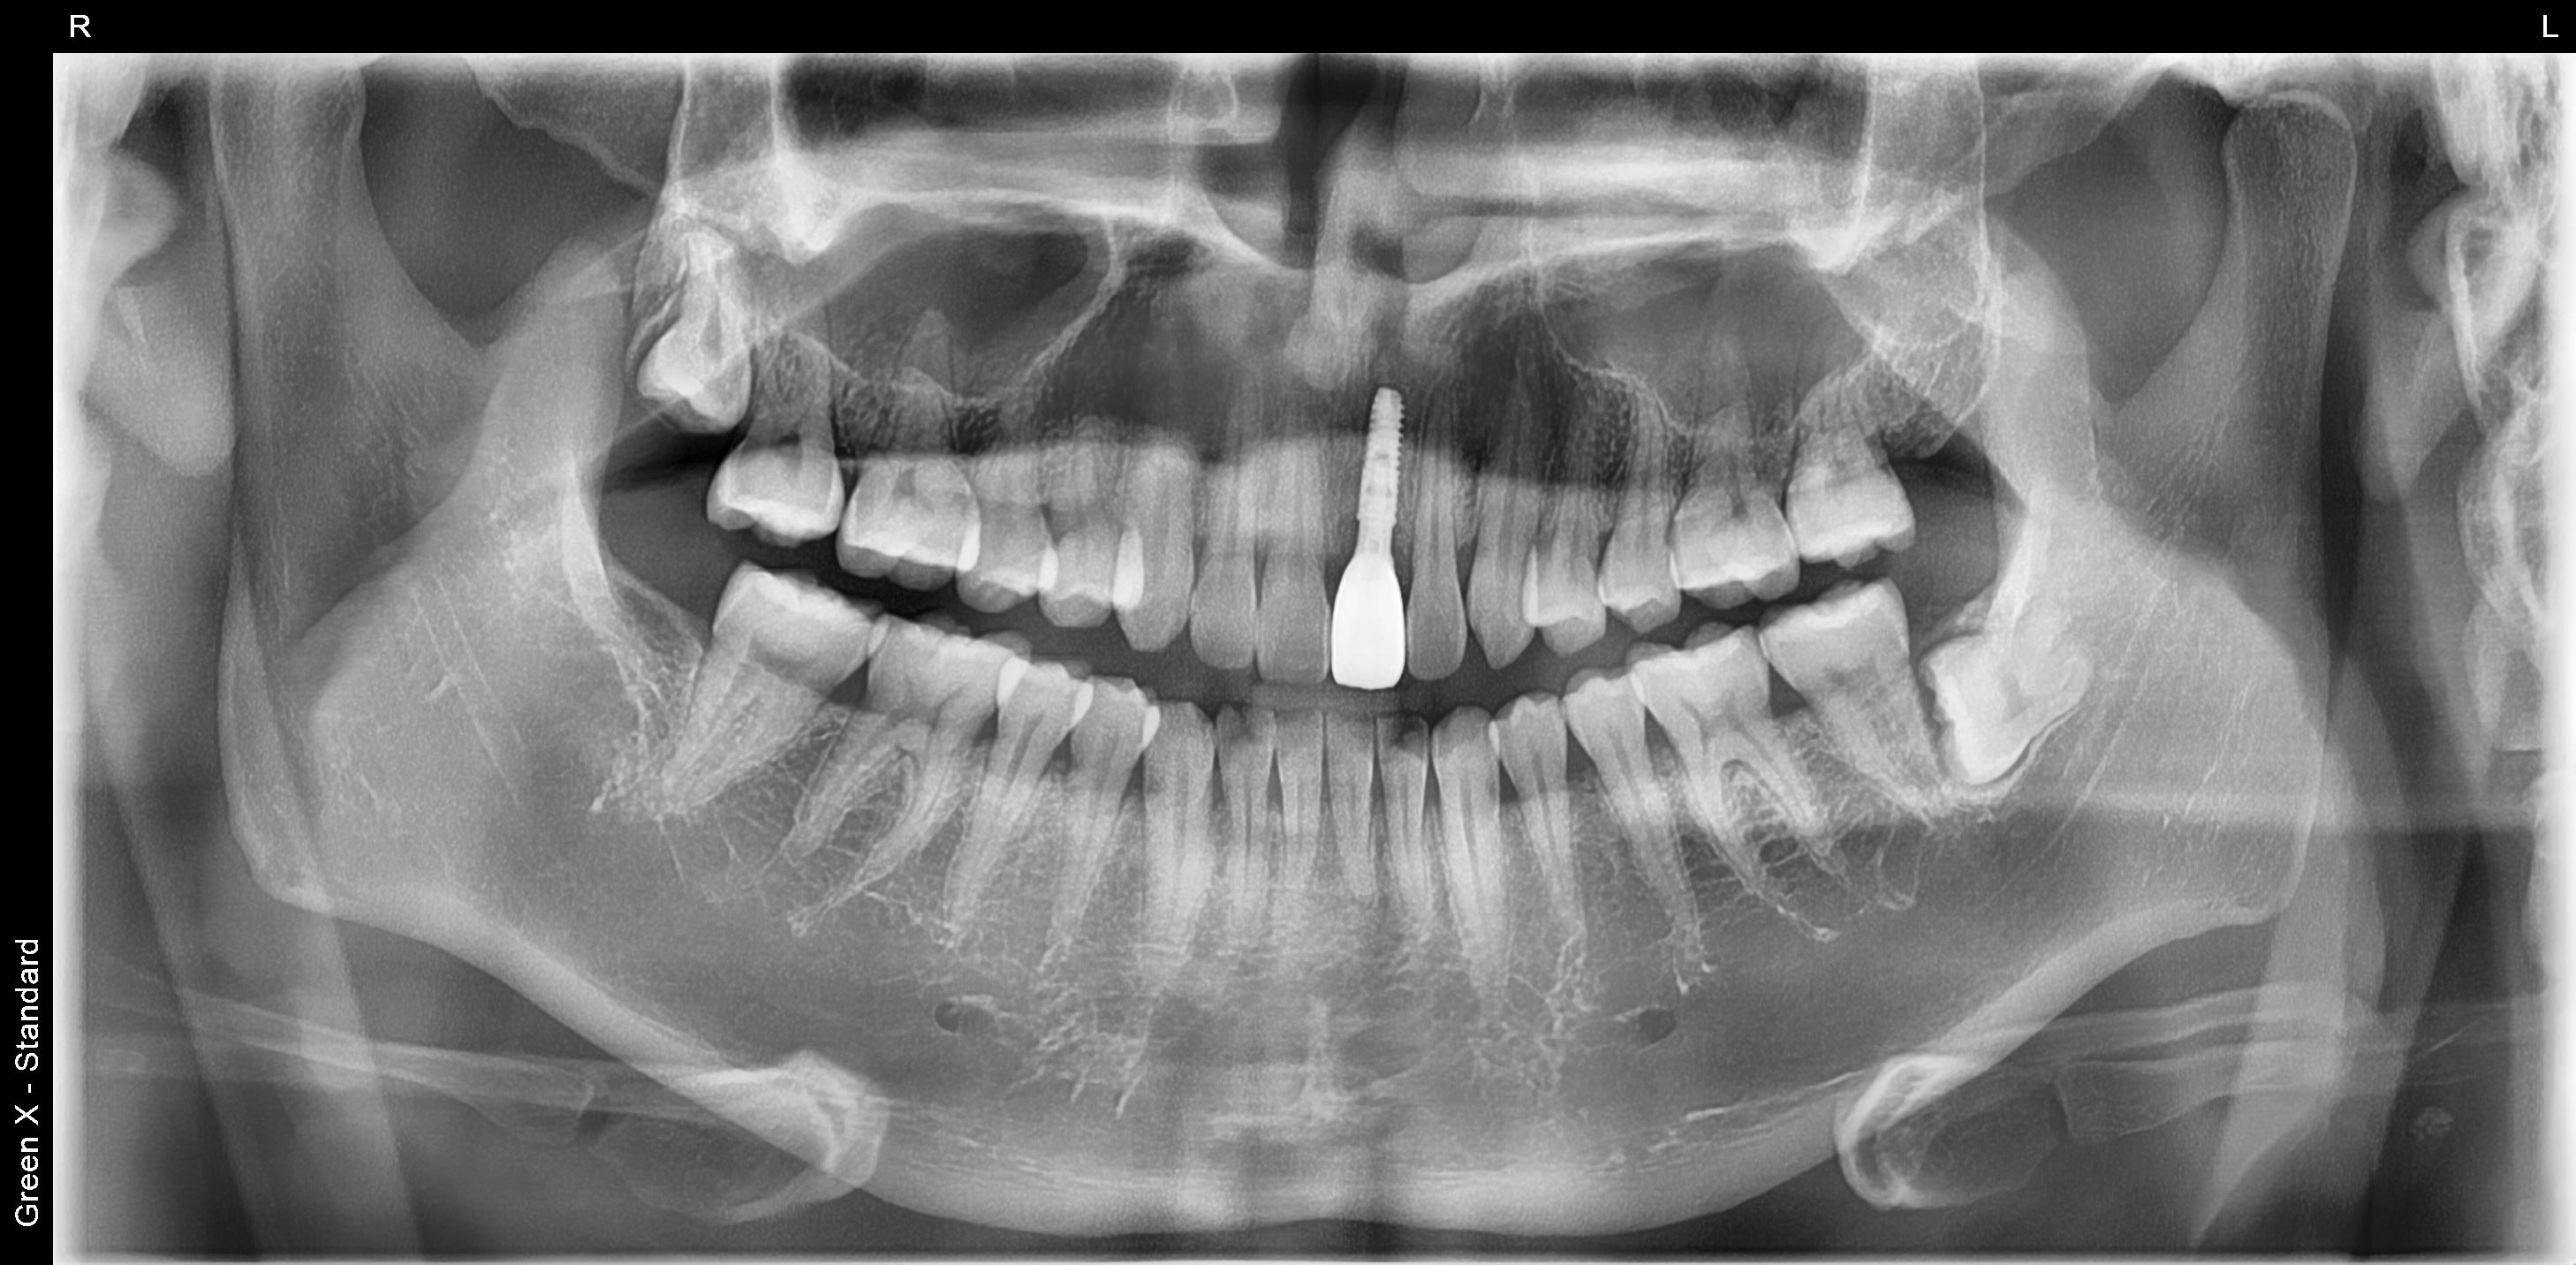

아래는 파노라마 엑스레이 사진입니다.